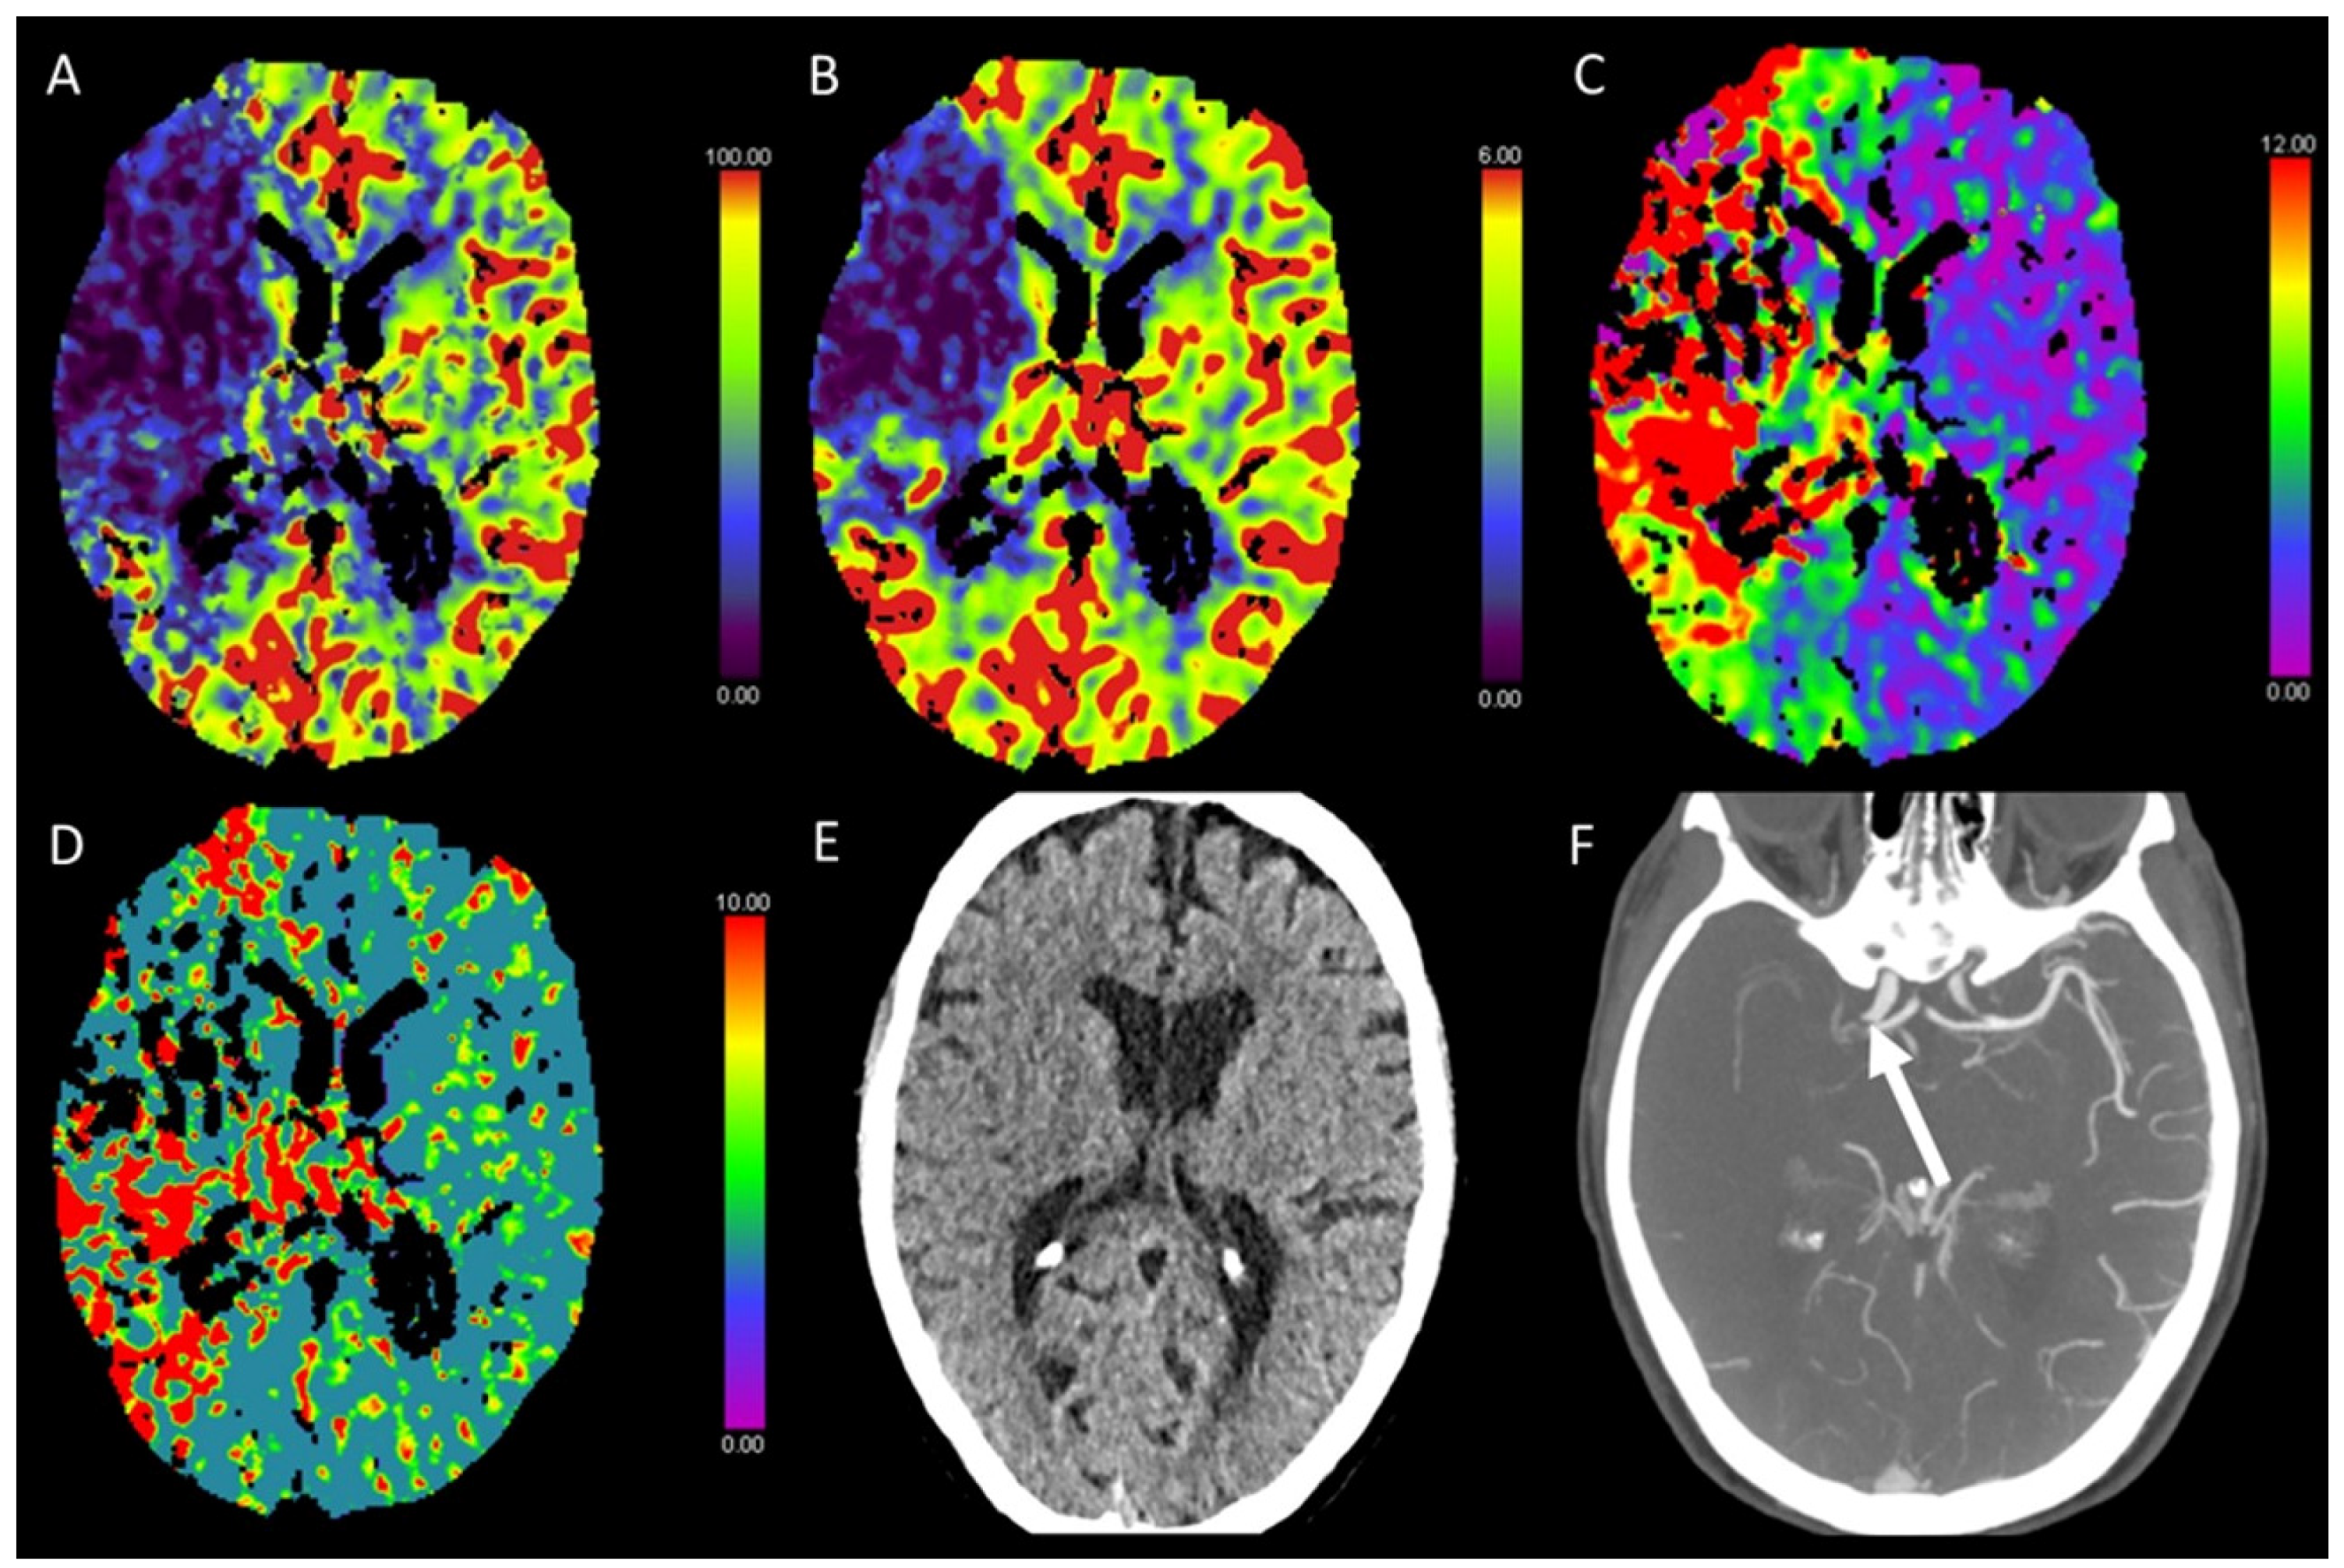

3.1. Acute Supratentorial Stroke

3.6. Vasospasm